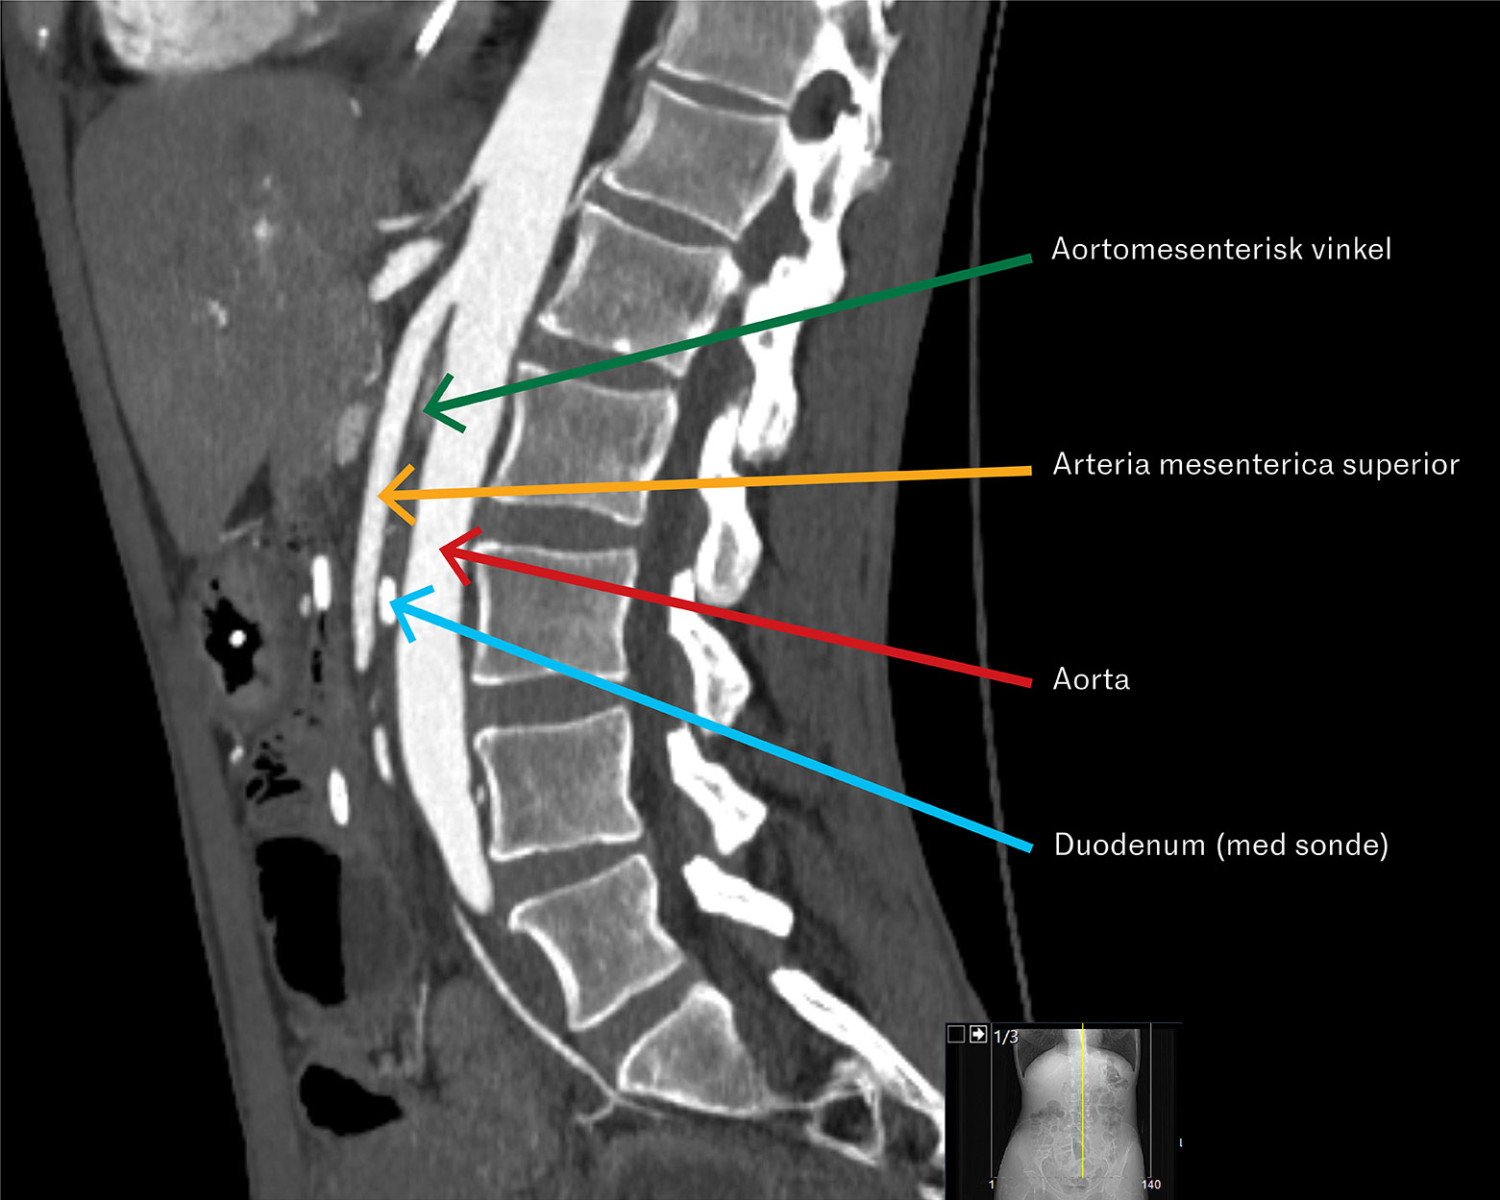

CT-bildet viser et sagittalt snitt av buken med funn av trang vinkel mellom arteria mesenterica superior og abdominalaorta, som sammen med symptomer og endoskopifunn ga diagnosen a. mesenterica superior-syndrom.

På bakgrunn av pasientens symptomer og funn av ventrikkelretensjon ved gastroskopi ble a. mesenterica superior-syndrom mistenkt (se illustrasjonen). CT-angiografi av abdominalkarene viste en vinkel mellom aorta og avgangen av a. mesenterica superior på 18 grader (normalt er > 25 grader) og aortomesenterisk avstand i nivå med duodenum på 5 mm (normalt er > 10 mm). Funnene var forenlig med diagnosen (1).